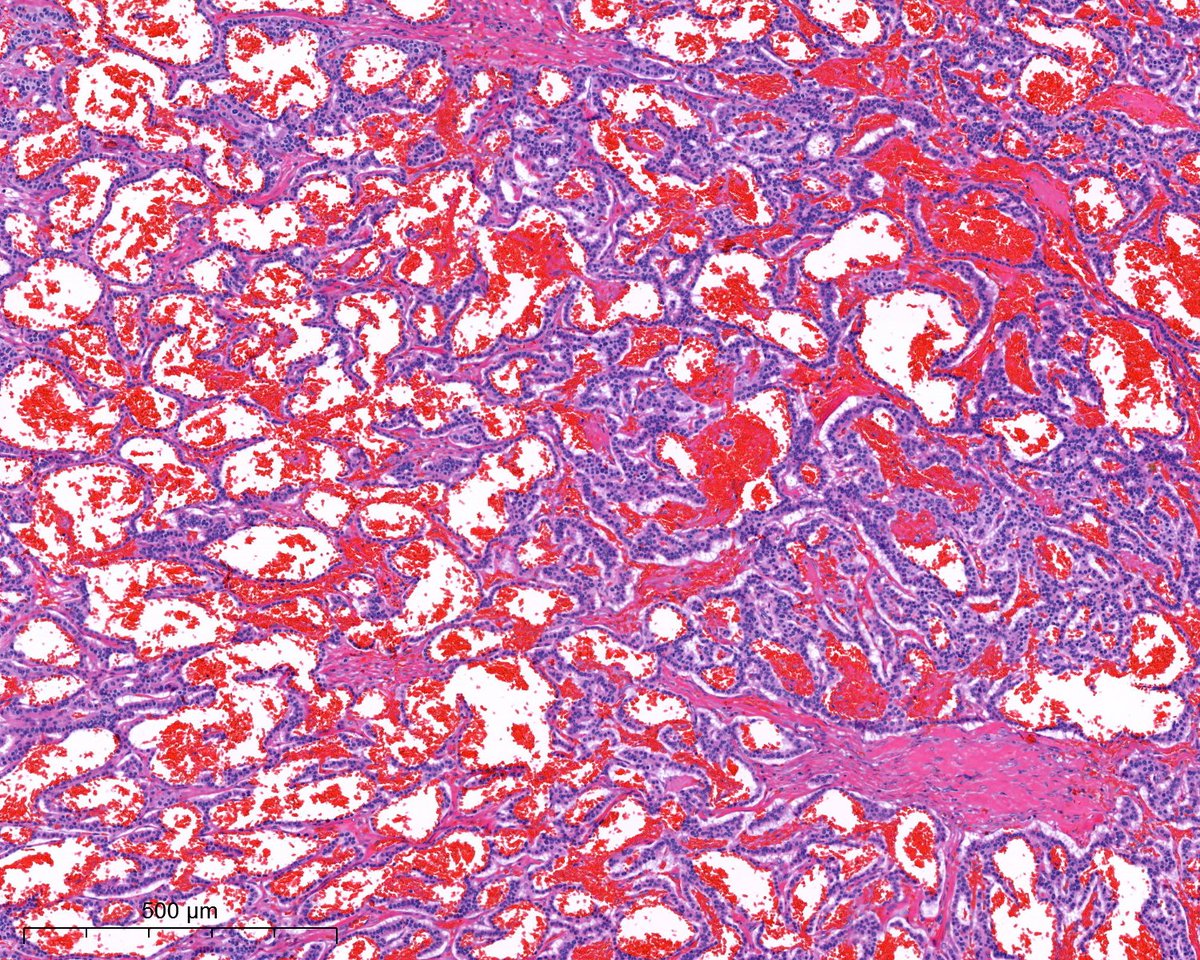

1. cistern formation 2. p57 negative in the villi, but positive in intervillous trophoblast (internal control). Complete mole is paternally derived and partial has maternal component, so p57 positive #pathtwitter #pathresidents

israhkhan's tweet image. 1. cistern formation

2. p57 negative in the villi, but positive in intervillous trophoblast (internal control).

Complete mole is paternally derived and partial has maternal component, so p57 positive #pathtwitter #pathresidents